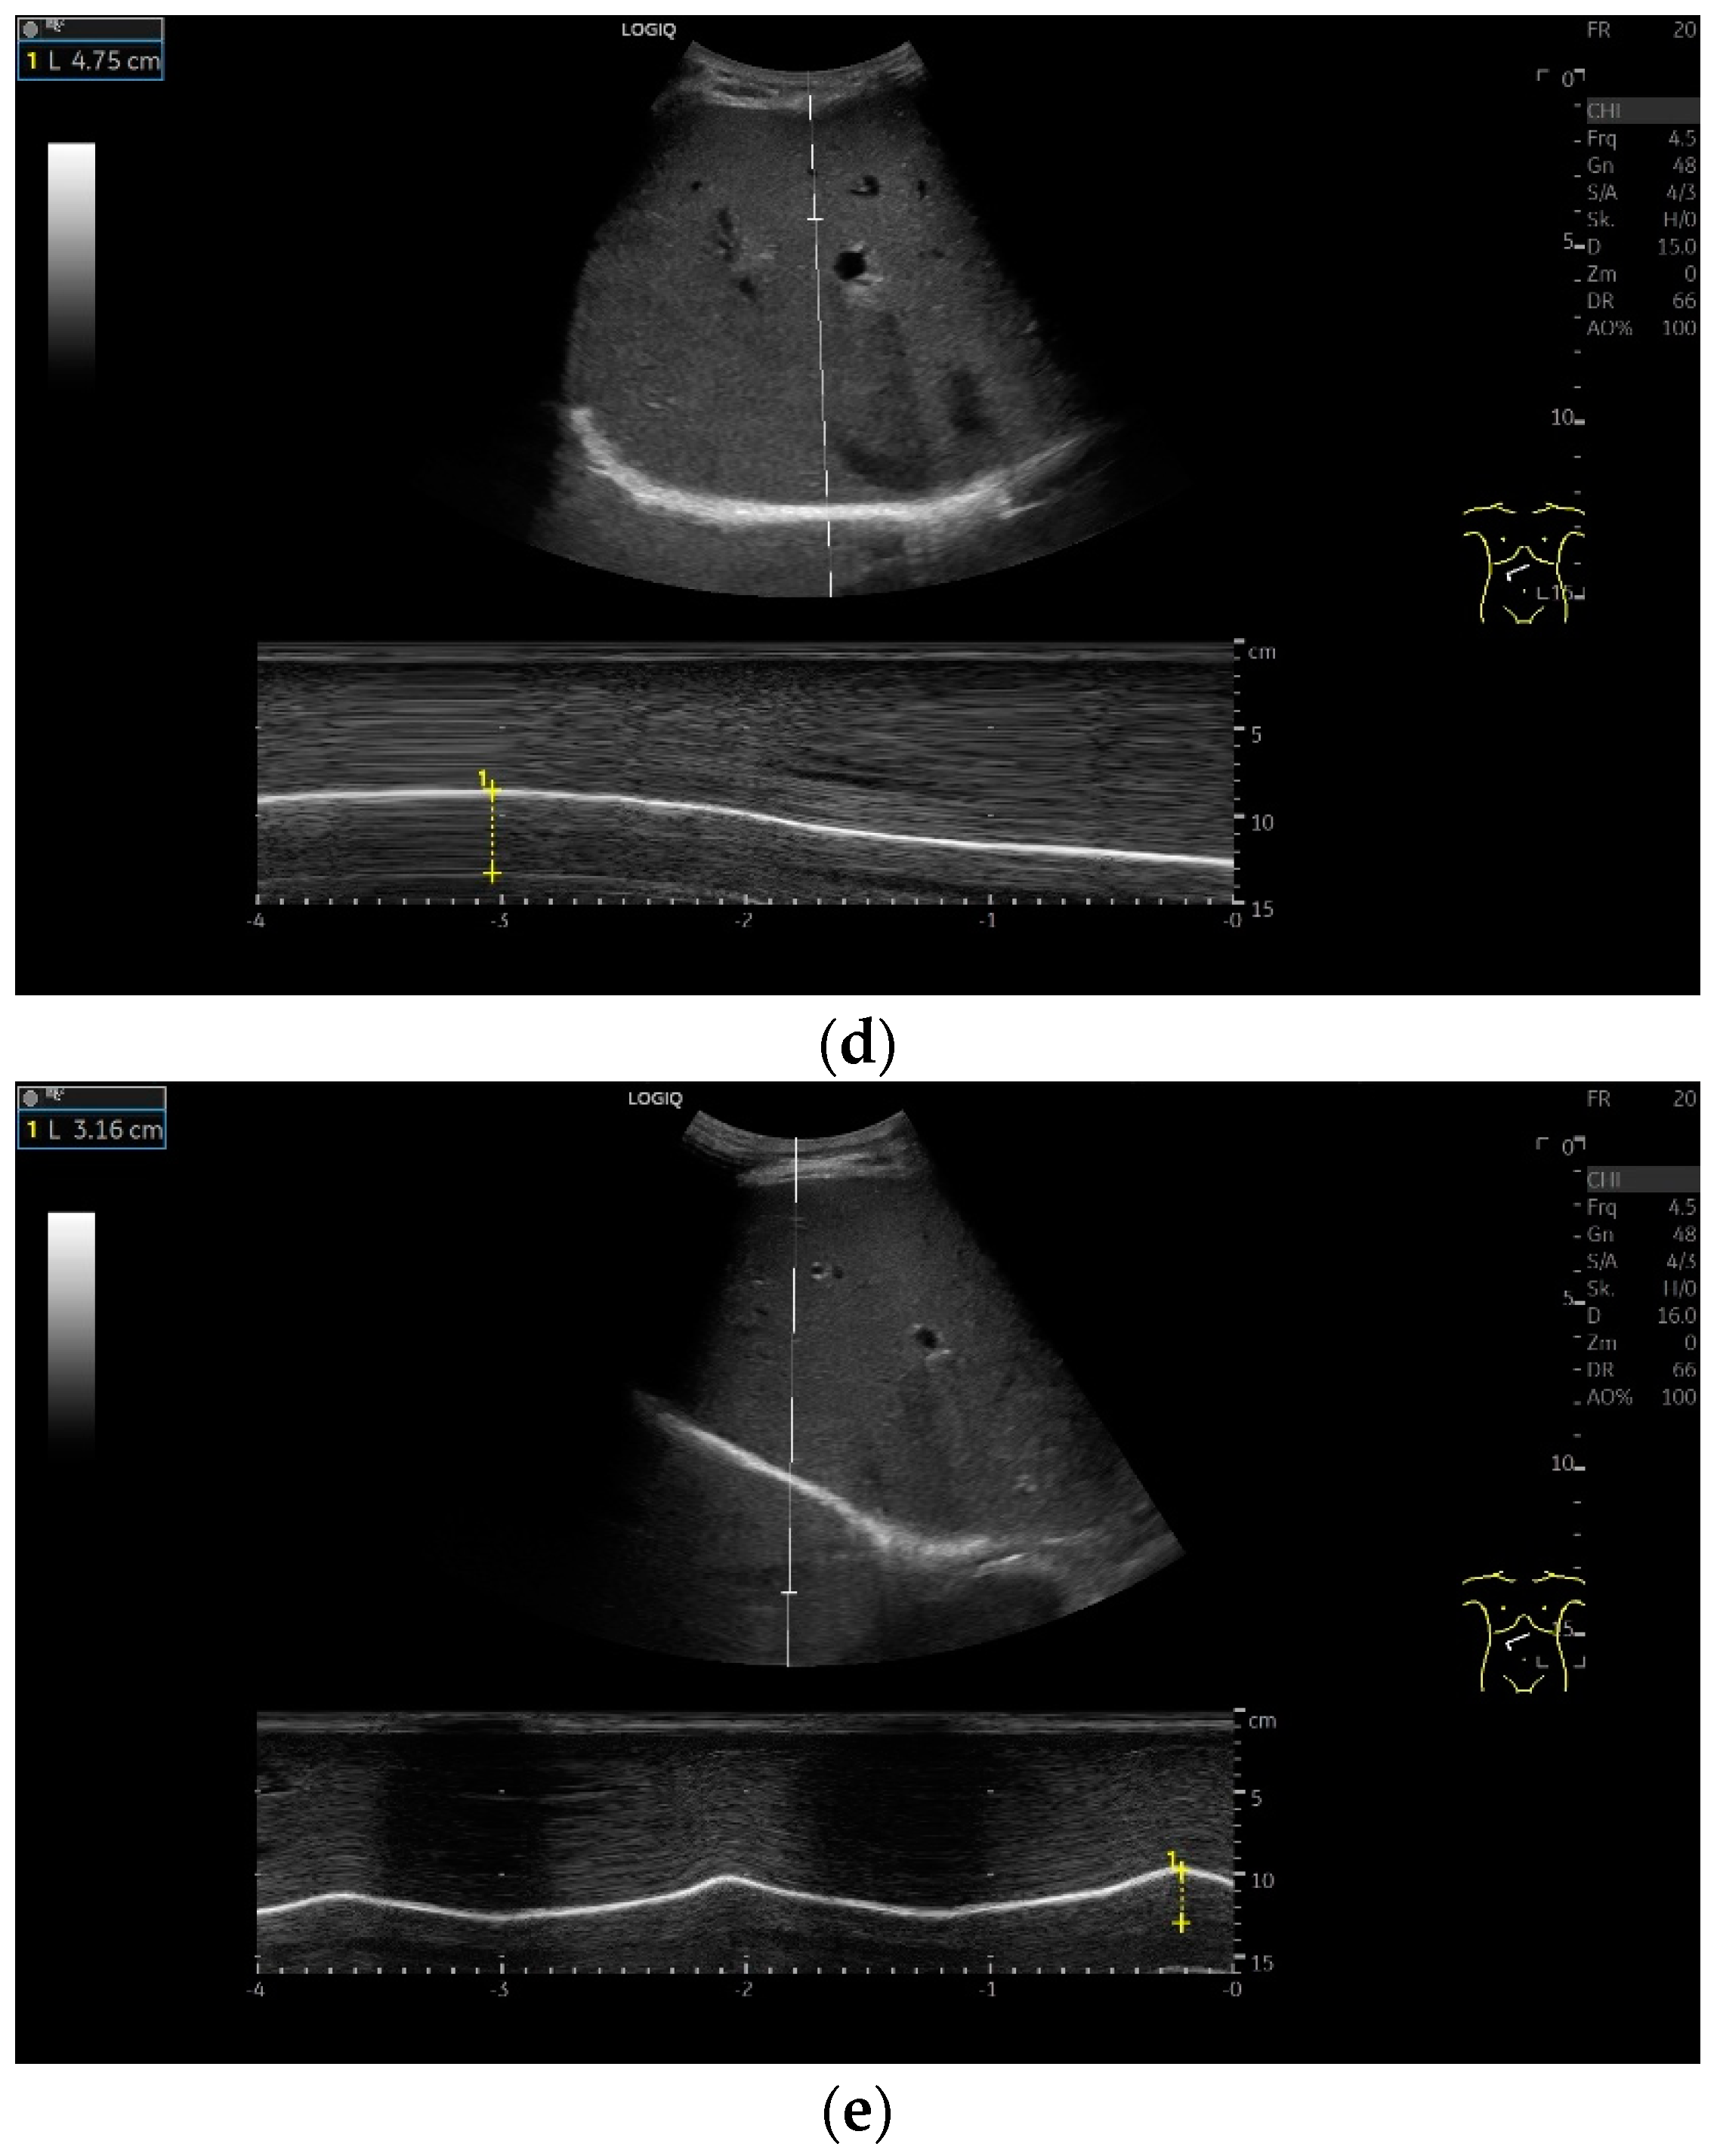

Subcostal transducer position: An abdominal sector or cardiac transducer (2–5 MHz) is used in the subcostal window. This position is used to assess diaphragmatic excursion. The transducer is placed between the linea medioclavicularis and linea axillaris anterior. The diaphragmatic excursion can then be visualized and measured in M-mode (Figure 5). The gallbladder and inferior vena cava are important landmarks. It is important to guide the ultrasound probe as perpendicularly as possible. The M-mode axis should meet the diaphragm at an angle of 90%. In this position, diaphragm thickness in inspiration and expiration can also be measured using M-mode, and diaphragm shortening can be calculated. However, in normal adults, the diaphragm can usually only be visualized in this position using abdominal sector transducers and is less accurately delineated than with a linear transducer from the lateral side in the anterior axillary line.

To assess the diaphragm and its function, the diaphragm’s thickness, contraction and excursion are determined. Diaphragm thickness is mainly measured in the zone of apposition and excursion in the subcostal position. The diaphragm thickness is measured at end-expiratory (Tendexpir) and end-inspiratory (Tendinspir) points. Expiratory and inspiratory measurements should be taken with exactly the same transducer position. The measurement is taken at the outer edges of the hypoechoic muscle and at an angle of 90° to the diaphragm’s surface (Figure 4).

The diaphragm thickening ratio (TRdi) is calculated from these two parameters: thickness at end-inspiration divided by the thickness at end-expiration [8]. The reference value corresponds at 2.1 to 2.2 for quiet respiration [3,8]. In practice, this means that the end-inspiratory diaphragm is slightly more than twice as thick as the end-expiratory diaphragm. The diaphragm thickening fraction (TFdi) corresponds to the percentage increase in diaphragm thickness during inspiration: (end-inspiratory diaphragm thickness−end-expiratory diaphragm thickness)/end-expiratory diaphragm thickness × 100. The reference value is >36–37% in quiet breathing [9,10]. The calculations can be based on both B-mode and M-mode data of Tendexpir and Tendinspir.

Diaphragmatic excursion and amplitude reflect the range of mobility and contraction. They can be assessed using different breathing maneuvers: during quiet breathing, with deep inspiration and during sniffing. A sniff maneuver is a short, forced inspiration. The movement of the diaphragm is ideally mapped in M-mode. The amplitude of diaphragmatic movement can then be measured on the M-mode curve, as can the speed of the diaphragm excursion. Standard values in numerous studies for diaphragm thickness, contraction and movement amplitude depending on body position, gender and diaphragm side are listed in Table 1 and Table 2. In addition to mean values and standard deviations, various studies also report the lower limit of normality of diaphragm thickness and contraction as well as the derived parameters. These are limit values that indicate how high a parameter must be in order not to be considered pathological. In this way, patients with dysfunction can be identified. There is also information on the upper limit of normality. However, the meaning of such a value is not entirely clear.